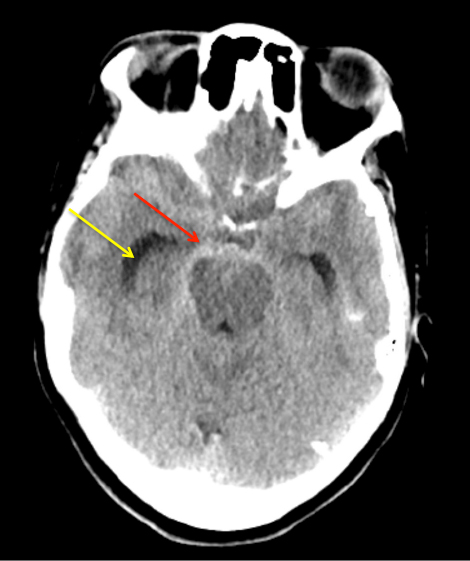

Urgent Cerebral Angiography confirmed a 5 mm posteriorly projecting aneurysm of the Basilar Artery Apex (Figure 2 A, B). Based on the location, morphology, and posterior projection, we decided to proceed to coil embolization of this high-risk aneurysm to prevent catastrophic re-bleeding and afford us the opportunity to maximize critical care for this patient during his hospital course. In this aneurysm, the dome-neck ratio was favorable from primary coiling, which was successfully performed resulting in near-complete embolization of the aneurysm (Figure 3 A, B). After 2 weeks of continued critical current l, endovascular, and neurosurgical care for complications of subarachnoid hemorrhage, including vasospasm and hydrocephalous, he was able to make a complete recovery and ultimately discharged home to complete his recovery, having regained all neurologic functions and activities of independent daily living and planning a return to work as an executive professional in the near future.

Figure 2: A) AP DSA angiogram demonstrates a 5 mm posteriorly projecting aneurysm of the Basilar Apex B) 3D DSA confirms the morphology and favorable dome to neck ratio for primary coil embolization.